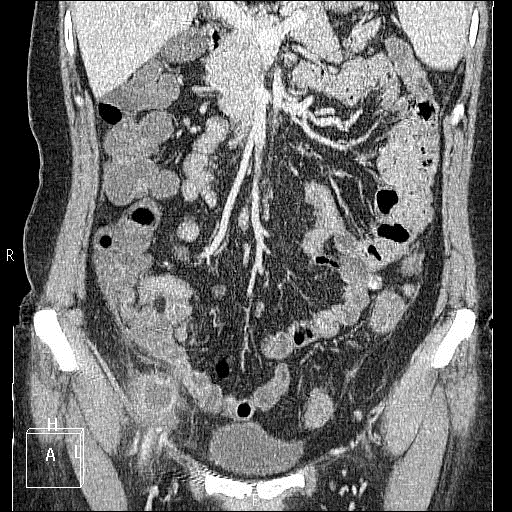

Диагностика. При аппендикулярном абсцессе в крови отмечается высокий лейкоцитоз. При динамическом наблюдении возможна температура гектического характера. Постепенно увеличивается инфильтрат, что сопровождается болезненностью в подвздошной области справа. УЗИ помогает узнать размер и точную локализацию гнойника. При проведении рентгеноскопического исследования органов брюшной полости вероятно выявление пневматоз и уровни жидкости в правой половине живота, что зачастую свидетельствует о явлениях паралитической непроходимости в кишечнике.